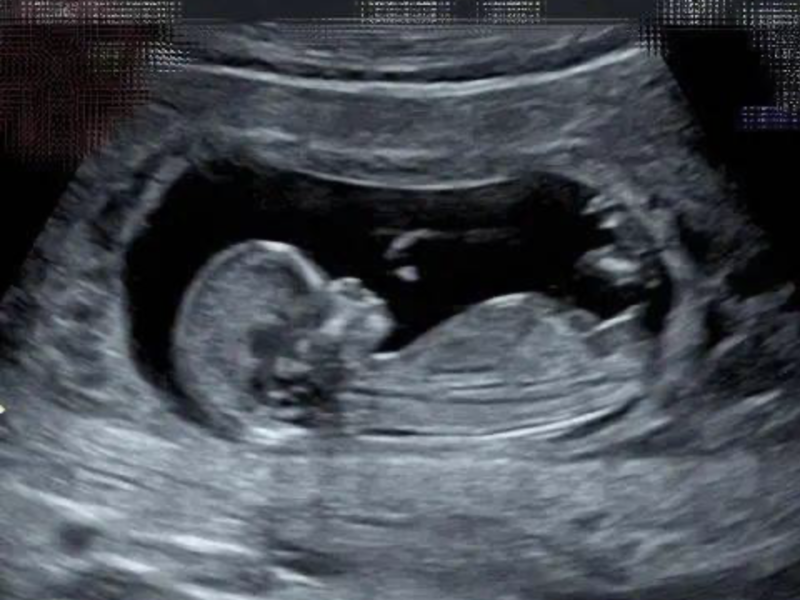

这款创新性的可穿戴贴片十分轻薄,面积大约在10 - 14平方厘米之间。它具备精准监测胎儿各种动作的能力,无论是胎儿的翻滚、伸展,还是踢腿等细微动作,都能被它敏锐捕捉。在针对59名孕妇开展的临床试验中,该设备展现出了卓越的性能,识别这些胎儿动作的准确率超过了90%,数据可靠性极高。

胎动作为反映胎儿健康状况的关键信号,其重要性不言而喻。然而,长期以来,在医院外缺乏一种简便又舒适的监测方式。目前,孕妇在家中大多依靠自我计数的方式来感知胎动,但这种方式存在明显弊端。一方面,自我计数容易产生不确定性,孕妇可能难以准确判断胎动的次数和强度;另一方面,这种不确定感还可能给孕妇带来额外的心理负担,影响其孕期情绪和生活质量。